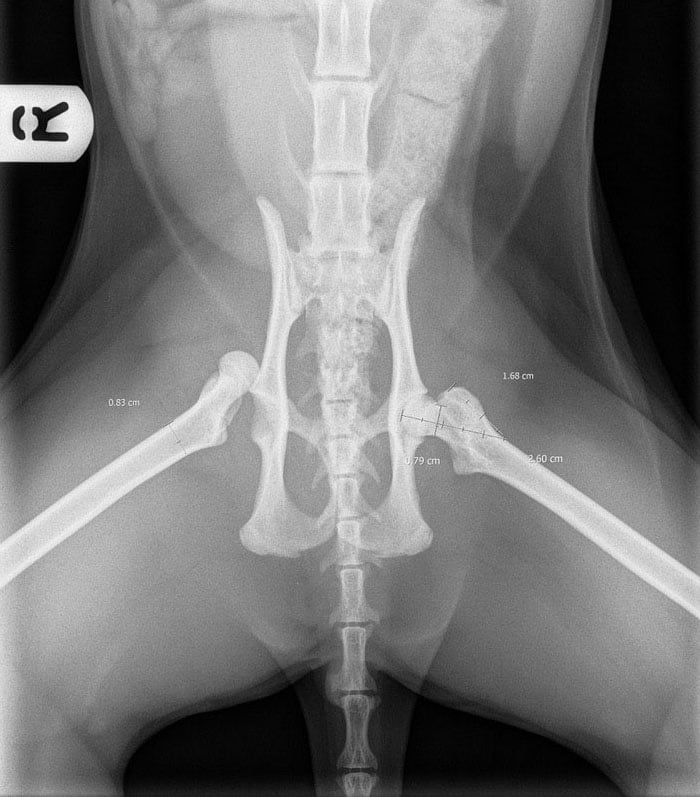

Figure 1 from Fixation of pelvic floor fractures in cats. Semantic How To Fix A Cat S Broken Hip Discuss treatment options for the fracture. The aim of treating a broken leg is to help the body heal the fracture as quickly as possible, and to return your cat to being able to use their limbs naturally and painlessly as before. All cats with broken limbs will require pain relief and rest, but the specific nature of the treatment. How To Fix A Cat S Broken Hip.

Figure 2 from Fixation of pelvic floor fractures in cats. Semantic How To Fix A Cat S Broken Hip Discuss treatment options for the fracture. Fho surgery can be an effective and relatively inexpensive surgical treatment option for cats suffering from hip problems. The cost of your cat's surgery will depend upon a number of. The aim of treating a broken leg is to help the body heal the fracture as quickly as possible, and to return your cat. How To Fix A Cat S Broken Hip.